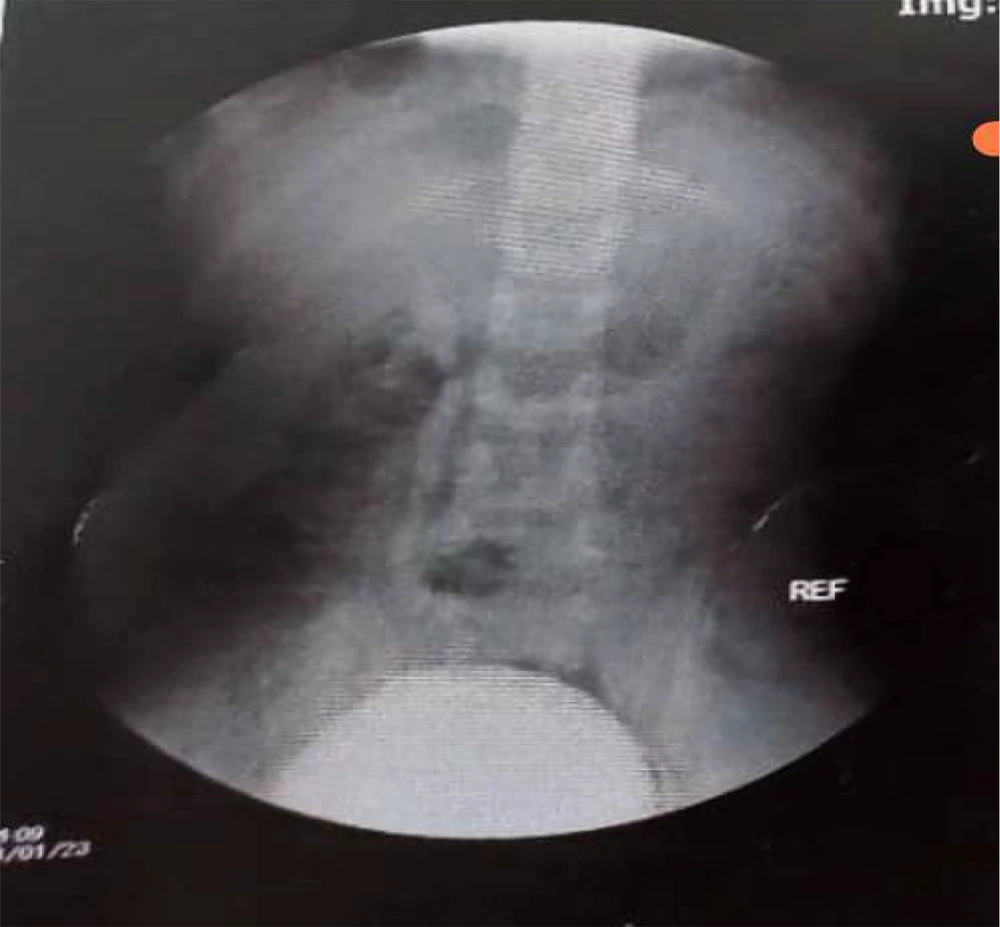

A few days later, the patient returned to our clinic with fever, abdominal pain, and dysuria. Physical examination revealed no significant findings. Urine analysis was conducted, revealing P. aeruginosa resistant to all antibiotics. The patient was admitted, and treatment with meropenem was initiated. Further evaluation, including a voiding cystourethrogram (VCUG) (Figure 1), revealed high-grade right urinary reflux. A dimercaptosuccinic acid (DMSA) scan showed significantly reduced size and contrast uptake in the right kidney. Laboratory data are presented in Table 1.